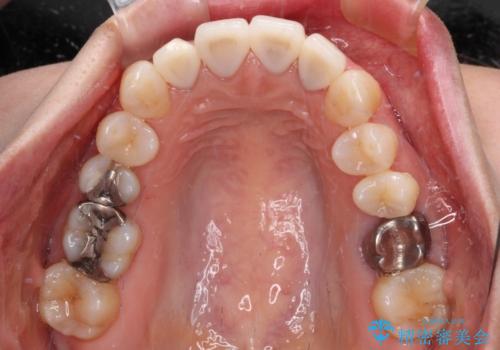

- 上顎4前歯に装着されているセラミッククラウンのうち、ひとつが欠けてしまったとのことで来院された患者様です。

土台となっている歯には問題がないため、周囲のセラミッククラウンと色調が合うように、オーダーメイドタイプのセラミッククラウンにて補綴治療を行うこととしました.

欠けてしまったセラミッククラウンはガラス系セラミッククラウンであったため、今回製作する歯は、強度の強いジルコニアセラミッククラウンとしました。

クラウンの種類は異なりますが、色調の適合したクラウンを装着することができました。